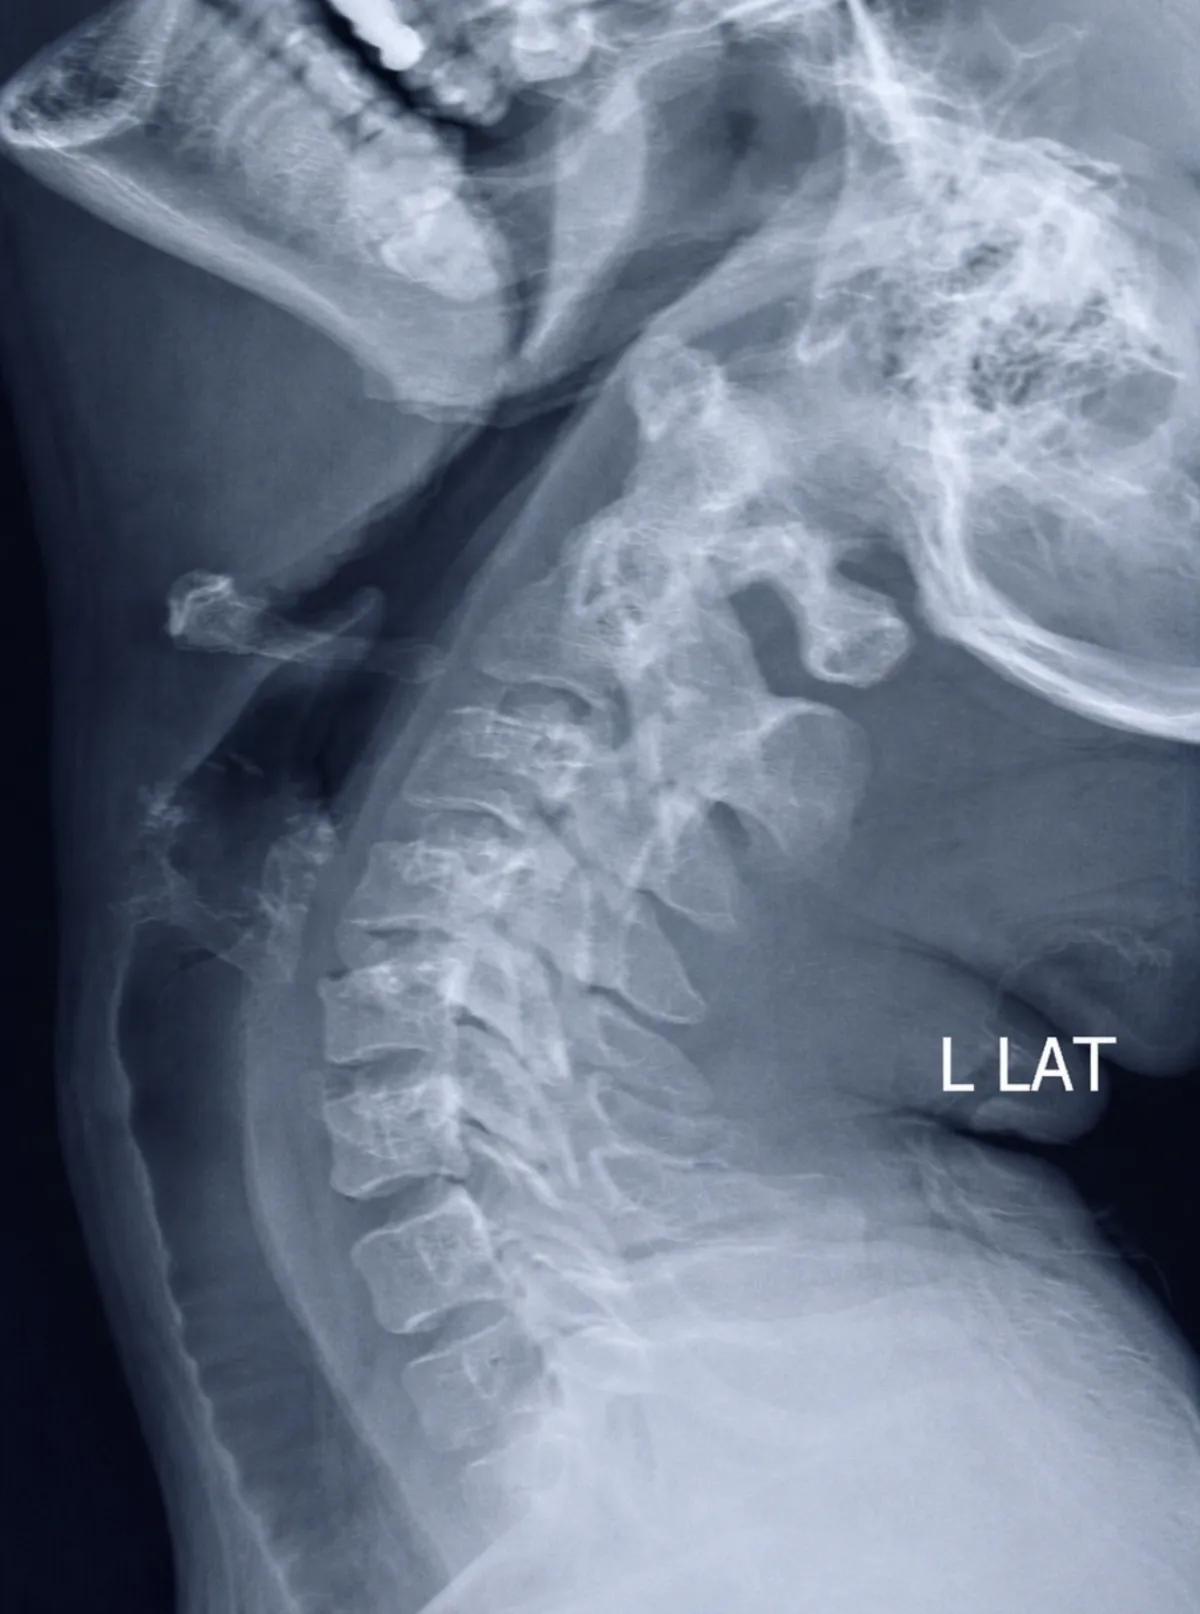

Spinal Instability & Symptomatic Disk, Joints and Ligaments

Platform identifies imaging findings related to spinal instability, symptomatic disc abnormalities, facet joint changes, and ligamentous injuries for physician review and clinical correlation.

Multi-Level Spine Analysis Example

Imaging shows findings consistent with instability at L4/5 and L5/S1 following prior percutaneous disc procedure. Board-certified physician review recommended for treatment planning.